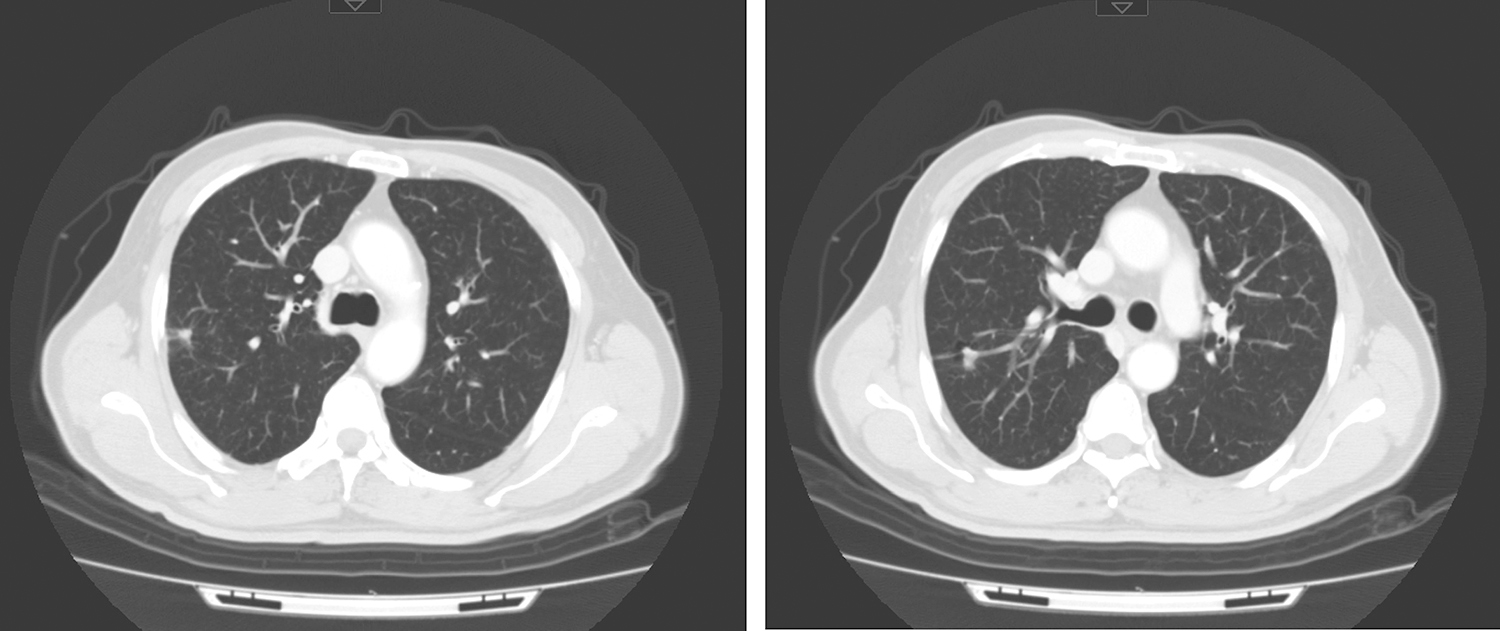

11.2018年1月11日颈胸CT,喉癌术后、化疗后复查,与2017年11月1日颈胸部CT图像比较:

(4)右肺上叶后段多个结节较前缩小,现大者约1.5cm×0.8cm(图6),请结合临床并随诊。余双肺可见多发小结节,较前缩小,大部分已显示不清,现大者约0.2cm,建议随诊。

图6 右肺上叶后段多个结节较前缩小

引自:头颈部肿瘤多学科诊疗病例精选.第1版.ISBN:978-7-117-27929-1.主编:李正江

12.2018年2月24日颈胸部CT,“喉癌术后、右肺鳞癌化疗后”复查,与2018年1月11日颈胸部CT图像比较。

(2)右肺上叶后段不规则结节,余双肺多发微结节(图7),均同前大致相仿,建议继续随诊。

图7 右肺上叶后段不规则结节

(3)左肺上叶及下叶背段新见多发小淡片影,余双肺多发斑片、索条影,同前相仿,以上均考虑为炎性病变,请随诊。双肺小叶间隔增厚,同前相仿。

(4)纵隔及左肺门多发淋巴结,同前相仿,现大者仍约0.9cm,建议随诊。双颈部未见明确肿大淋巴结。